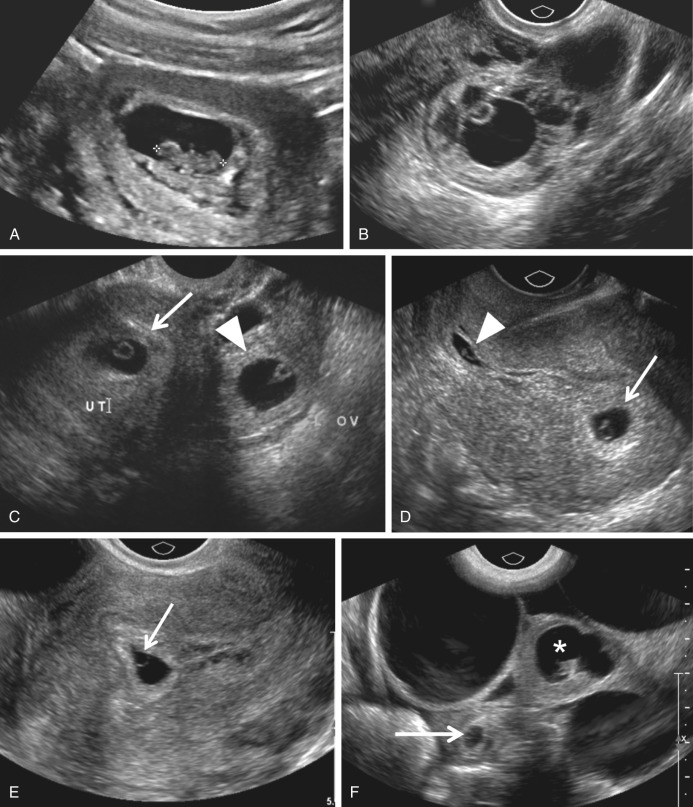

Transvaginal ultrasound demonstrating viability of twin pregnancy at 8 …

Ectopic Pregnancy | Radiology Key

Ectopic Pregnancy – Core EM

Ectopic Pregnancy: A Trainee’s Guide to Making the Right Call: Women’s …

Transvaginal ultrasound images of an ectopic cervical pregnancy: empty …